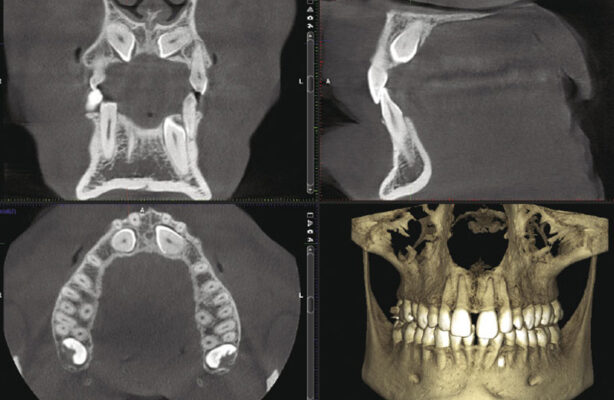

Khi thực hiện chụp phim CT Conebeam 3D, đầu máy sẽ xoay 360 độ quanh vùng hàm mặt trong vài giây để thu thập dữ liệu.

Hệ thống cảm biến đặc biệt sẽ ghi lại hàng trăm lớp cắt siêu mỏng của vùng cần khảo sát.

Chỉ với một lần chụp duy nhất, bác sĩ có thể quan sát hàng triệu góc nhìn – từ trên xuống, từ dưới lên, mặt bên, mặt nghiêng…

Những dữ liệu này sau đó được xử lý bằng phần mềm chuyên dụng để tái dựng thành mô hình 3D sắc nét, phản ánh chính xác cấu trúc xương hàm, răng, chân răng, dây thần kinh và xoang hàm của người bệnh.

Từ đó dễ dàng phát hiện các vấn đề tiềm ẩn như tiêu xương, viêm quanh chân răng cũ, khoảng cách đến dây thần kinh, độ sâu xoang hàm… giúp quá trình lập kế hoạch điều trị trở nên chính xác và cá nhân hóa cho từng khách hàng.

- Đánh giá chính xác thể tích – mật độ xương hàm tại vị trí cần cấy Implant.

- Phát hiện các yếu tố nguy cơ như dây thần kinh, xoang hàm, viêm quanh răng cũ…

- Xác định bệnh nhân có cần ghép xương/nâng xoang hay không.

- Làm cơ sở để lập phác đồ điều trị bằng phần mềm CAD/CAM và sản xuất máng định vị HiSafe.

Hãy cùng nghe phân tích lâm sàng từ phim chụp CT Conebeam trường hợp mất gần hết răng và phương pháp điều trị phù hợp từ bác sĩ Trần Mạnh Toản – BS Phục hình Tiểu phẫu tại Nha khoa Vân Anh: